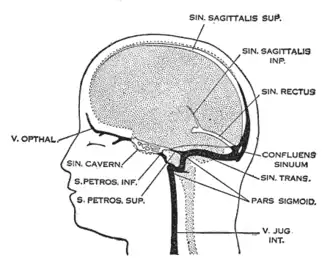

Венозный отток от головного мозга | |

Тромбоз синусов твёрдой мозговой оболочки — редкая форма нарушения мозгового кровообращения, представляющая собой ухудшение оттока крови от головного мозга из-за закупорки синусов кровяными сгустками (тромбами). Проявляется головной болью, нарушением зрения, гемипарезом лица или конечностей, судорогами и др. Диагноз устанавливается на основе данных компьютерной или магнитно-резонансной томографии с внутривенным контрастным усилением, позволяющих визуализировать обструкцию венозных синусов тромбом.[1] Для лечения применяется терапия антикоагулянтами, реже — тромболитиками. Так как данная патология обычно является осложнением другого заболевания, может потребоваться дополнительное обследование. Тромбоз венозных синусов может осложниться внутричерепной гипертензией, для купирования которой в некоторых случаях применяется хирургическое вмешательство (например, шунтирование).[1]